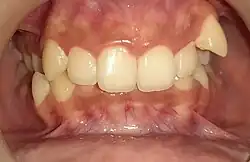

Глубокий прикус (overbite) — аномалия соотношения зубных дуг, вид патологического прикуса, при котором нарушено смыкание зубов в вертикальной плоскости. При таком прикусе верхние передние зубы перекрывают нижние передние зубы больше, чем на половину.[1] Чрезмерно глубокий прикус относится к классу II по классификации Энгла.

Степень перекрытия верхними нижних зубов верхними называется английским термином overbite и часто измеряется в процентах. В норме overbite составляет от 30% до 50%. При отродонтическом лечении overbite чаще измеряют в абсолютных значениях в миллиметрах, используется расстояние от края верхнего резца до края нижнего резца.[2]